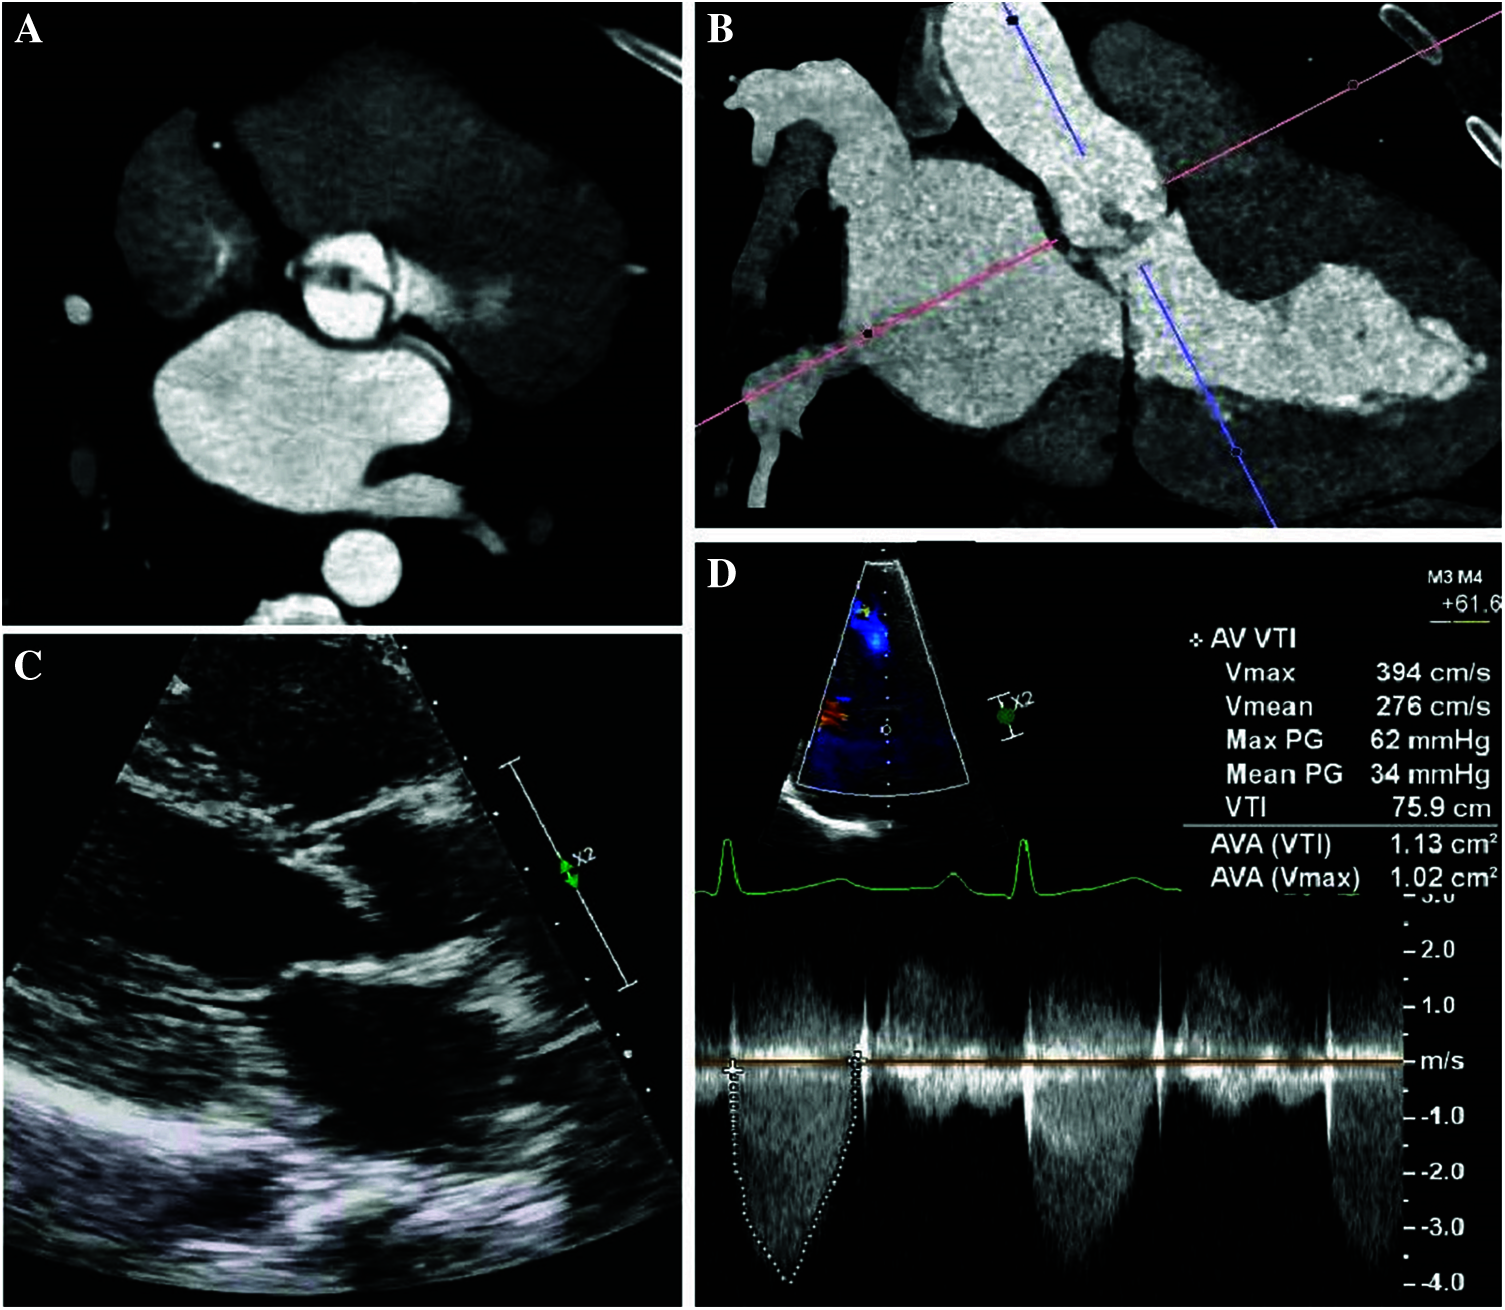

Figure 3: Cardiac imaging of Patient 3 with Shone complex showcasing abnormalities of her aortic valve

Panel A: Tomographic imaging demonstrating fusion and thickening of the aortic cusps in a patient with a suspected unicuspid aortic valve.

Panel B: Tomographic imaging in the coronal axis demonstrating thickening of the aortic cusps.

Panel C: Echocardiography (parasternal long axis image) demonstrating thickening of the aortic cusps and eccentric closure of the parachute mitral valve.

Panel D: Continuous wave Doppler across the stenotic aortic valve revealing a peak aortic jet velocity of 3.9 m/s and a mean gradient of 34 mmHg.